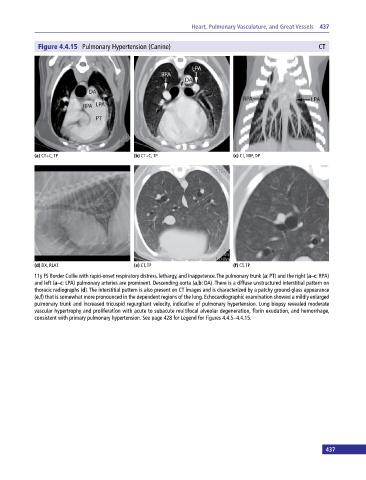

Figure 4.4.15 Pulmonary Hypertension (Canine) CT

(a) CT+C, TP (b) CT+C, TP (c) CT, MIP, DP

(d) DX, RLAT (e) CT, TP (f) CT, TP

11y FS Border Collie with rapid‐onset respiratory distress, lethargy, and inappetence. The pulmonary trunk (a: PT) and the right (a–c: RPA)

and left (a–c: LPA) pulmonary arteries are prominent. Descending aorta (a,b: DA). There is a diffuse unstructured interstitial pattern on

thoracic radiographs (d). The interstitial pattern is also present on CT images and is characterized by a patchy ground-glass appearance

(e,f) that is somewhat more pronounced in the dependent regions of the lung. Echocardiographic examination showed a mildly enlarged

pulmonary trunk and increased tricuspid regurgitant velocity, indicative of pulmonary hypertension. Lung biopsy revealed moderate

vascular hypertrophy and proliferation with acute to subacute multifocal alveolar degeneration, fibrin exudation, and hemorrhage,

consistent with primary pulmonary hypertension. See page 428 for Legend for Figures 4.4.5–4.4.15.